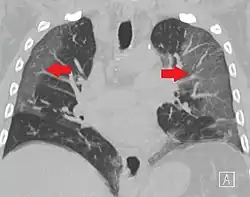

High-resolution CT image showing ground-glass opacities in the periphery of both lungs in a patient with COVID-19 (red arrows). The adjacent normal lung tissue with lower attenuation appears as darker areas.

CT image in patient with COVID-19 showing bilateral ground-glass opacities at the periphery of both lungs.

Ground-glass opacity is among the most common imaging findings in patients with confirmed COVID-19.[16][17] One systematic review found that among patients with COVID-19 and abnormal lung findings on CT, greater than 80% had GGOs, with greater than 50% having mixed GGOs and consolidation.[16] GGOs with mixed consolidation has most often been found in elderly populations.[18]

Several studies have described a pattern among initial, intermediate, and hospital discharge imaging findings in the disease course of COVID-19. Most commonly, initial CT imaging reveals bilateral GGOs at the periphery of the lungs. During initial stages, this is most often found in the lower lobes, although involvement of the upper lobes and right middle lobe has also been reported early in the disease course.[16][18] This is in contrast to the two similar coronaviruses, SARS and MERS, which more commonly involve only one lung on initial imaging.[19][20] As the COVID-19 infection progresses, GGOs typically become more diffuse and often progress to consolidation.[11][18] This is sometimes accompanied by the development of a crazy paving pattern and interlobular septal thickening.[18] In many cases the most severe pulmonary CT abnormalities occurred within 2 weeks after symptoms began.[17] At this point, many individuals begin showing resolution of consolidation and GGOs as symptoms improve. However, some patients have worsening symptoms and imaging findings, with further increase in septal thickening, GGOs, and consolidation. These patients may develop lung "white-out" with progression to acute respiratory distress syndrome (ARDS) requiring treatment escalation.[17][21]